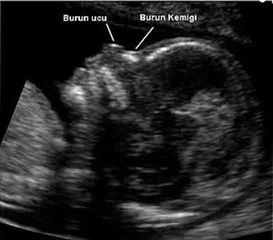

Anne Karnındaki İzleme ve DeğerlendirmeDown sendromu teşhisi konmuş bir hamilelikte, fetal hareketlerin izlenmesi, hem anne hem de bebek için önemlidir. Doktorlar, ultrason gibi yöntemlerle bebeğin hareketlerini değerlendirebilir ve anneden gelen geri bildirimler, bebeğin sağlığı hakkında önemli ipuçları sağlayabilir. Fetal Hareketlerin İzlenmesi İçin Yöntemler

Anne karnındaki izleme sürecinde, ultrasonografi gibi görüntüleme teknikleri, fetal hareketliliğin izlenmesinde etkili yöntemlerdir. Bunun yanı sıra, fetal kalp atış hızı monitörizasyonu, bebeklerin genel sağlığı ve hareketliliği hakkında ek bilgiler sağlayabilir. Bu yöntemler, fetal hareketliliğin değerlendirilmesi açısından önemli bilgiler sunabilir; ancak, Down sendromu gibi özel durumlar için daha detaylı incelemeler gerekebilir.